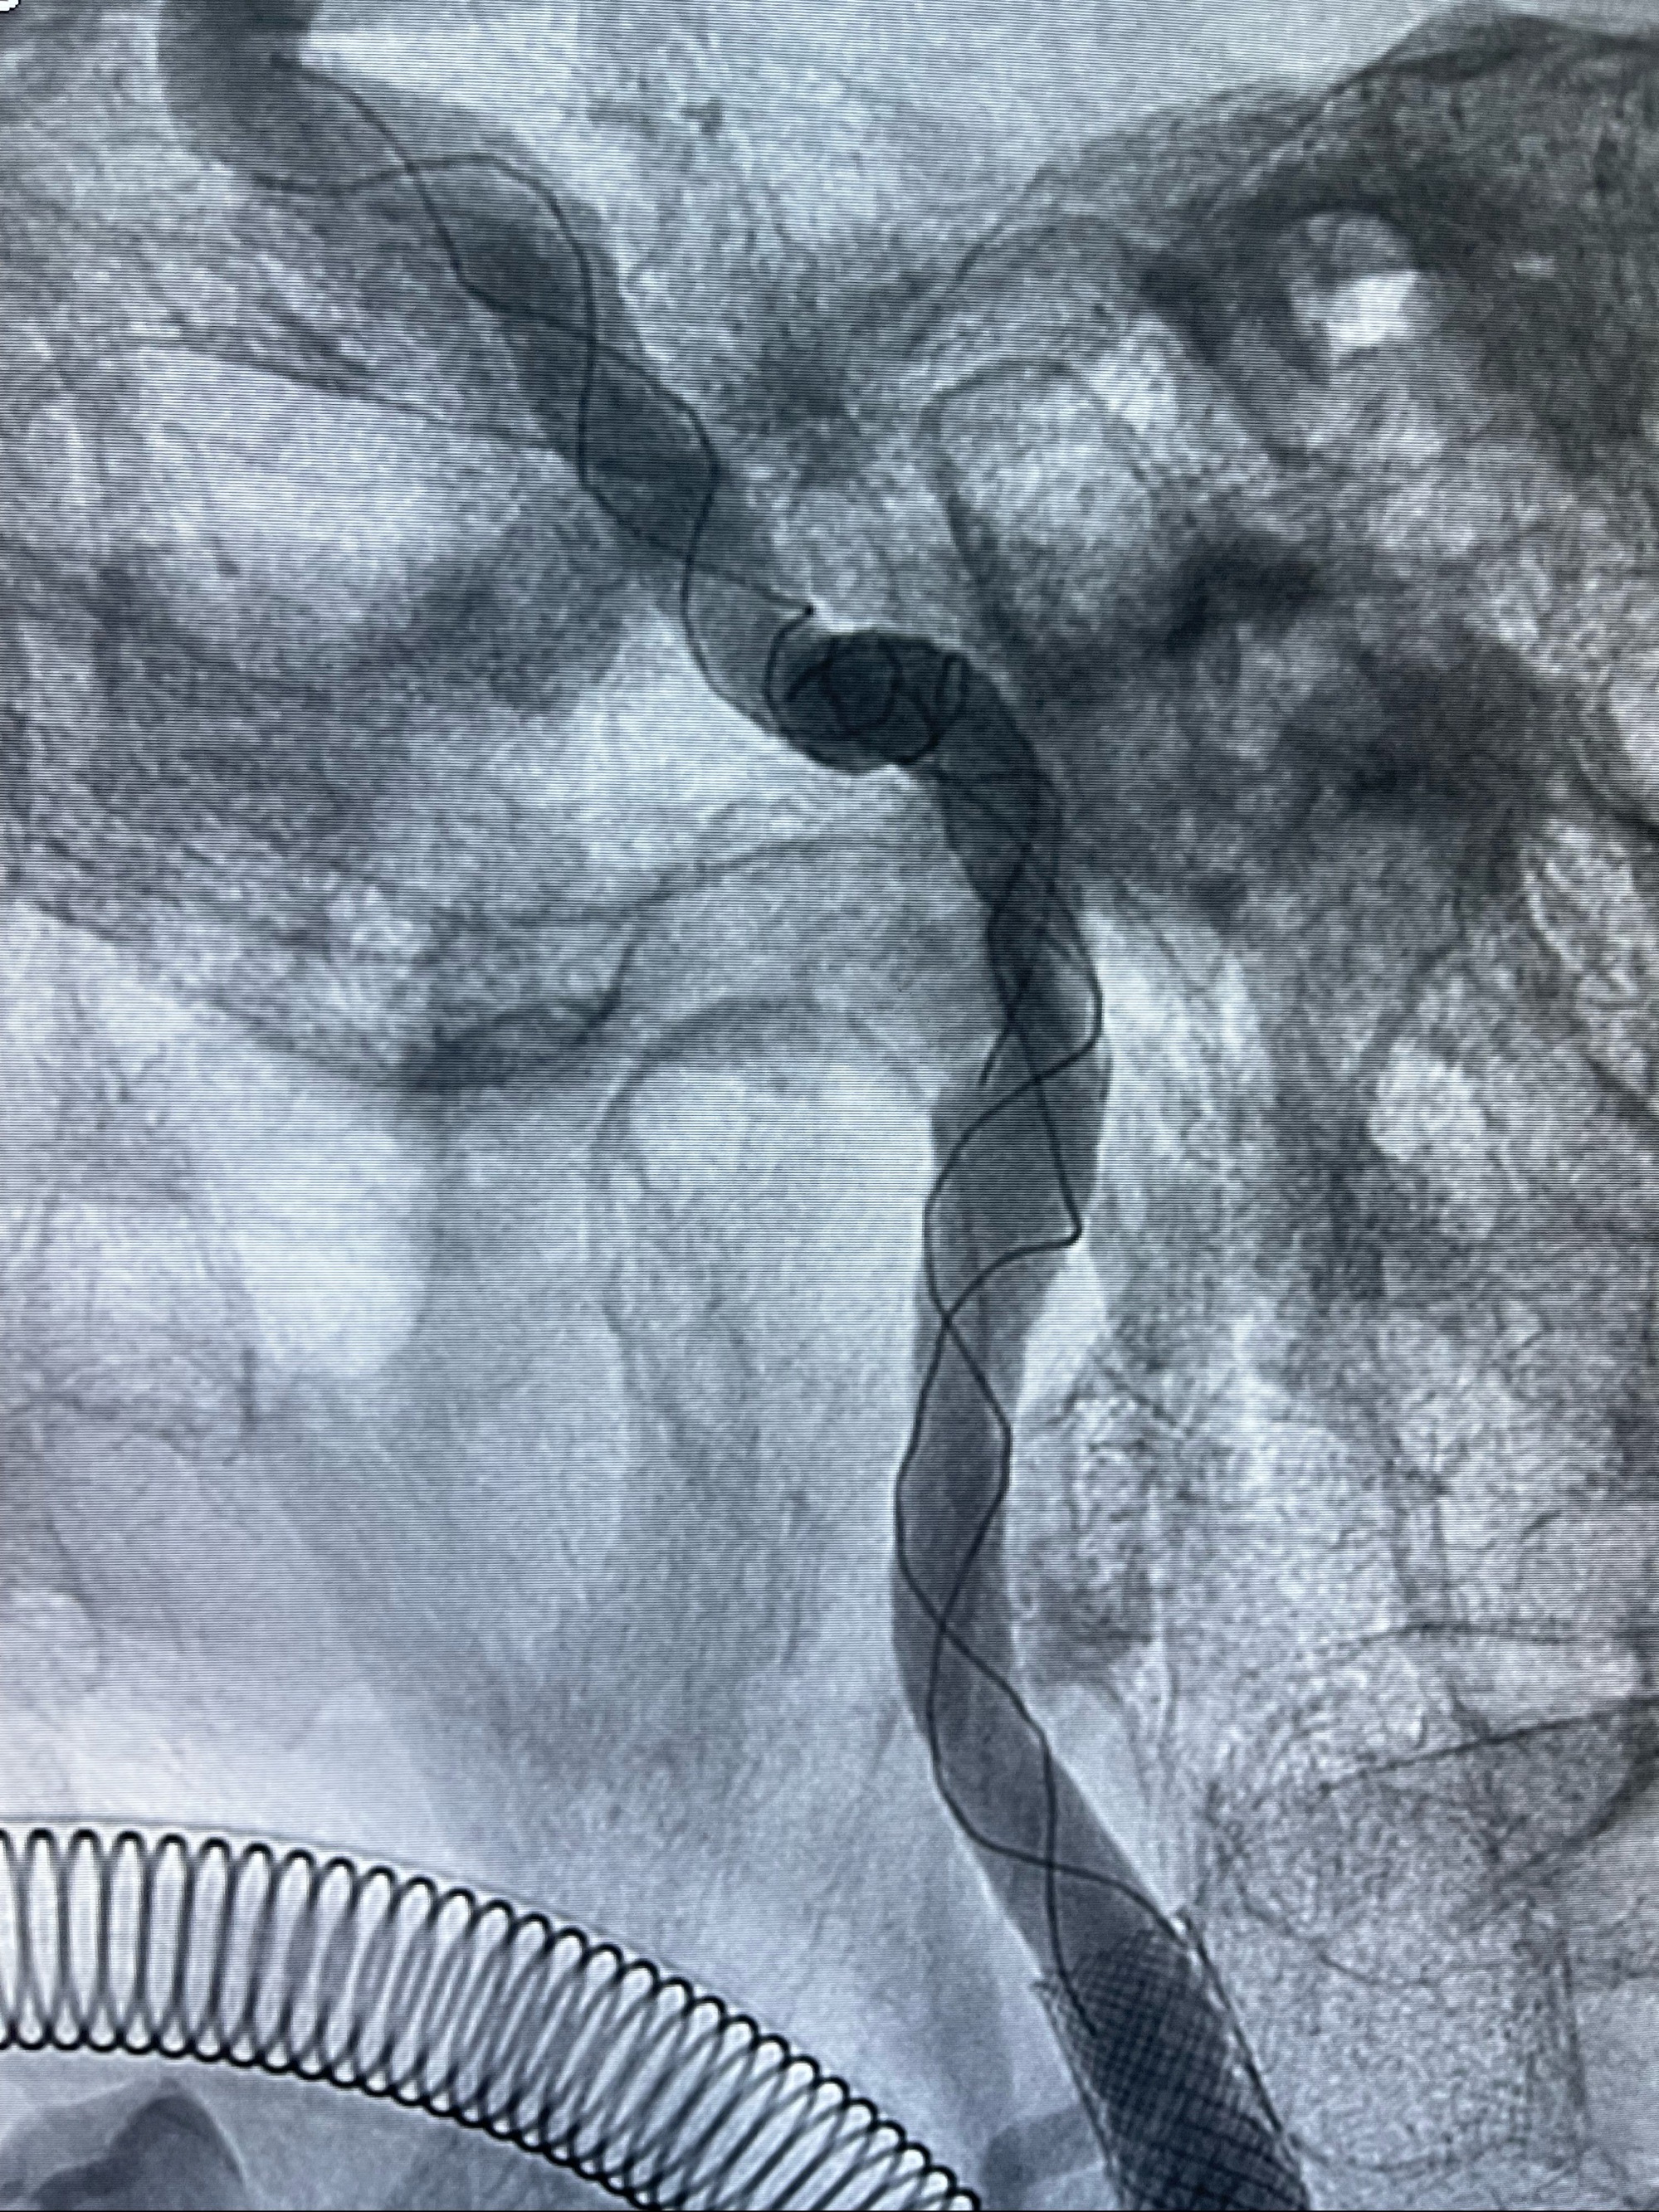

重新行“路径图”,支架导管在微导丝引导下超选择性插入至右侧颈内动脉眼段,4.5-50mmLeo支架释放,远心端位于海绵窦段,近心端位于岩骨段狭窄段以近

即刻造影显示支架贴壁佳

路径图下,5.5-50mmLeo支架导管在微导丝引导下超选择性插入远段Leo支架内

两枚支架部分重叠

多次确认支架位置及打开贴壁情况

支架完全打开,近心端位于原颈动脉支架远心端内